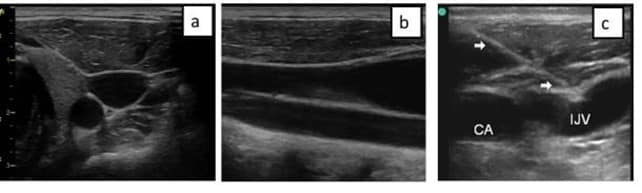

En el plano transversal, el haz de ultrasonidos corta el vaso perpendicularmente a su eje mayor, dando lugar a una sección circular.

- Permite una visualización amplia de todas las estructuras adyacentes a la vena a canalizar.

- No es posible realizar un abordaje en plano.

Para obtener el plano longitudinal, debemos realizar una rotación del transductor de 90º, desde el plano transversal, de esta forma visualizaremos la vena en el centro de la pantalla.

- Imposibilidad de visualizar las estructuras adyacentes a no ser que se encuentren en el mismo eje de la vena a nivel superior o inferior.

- Mayor complejidad técnica para la obtención de la imagen adecuada.